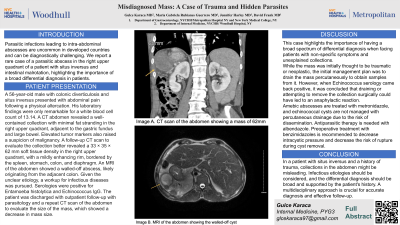

This case highlights the importance of a broad range of differential diagnoses for patients with non-specific symptoms and unexplained collections. Echinococcosis (hydatid disease) typically affects the liver and lungs, but can also involve the spleen, heart, kidney, or brain. Amebic abscesses are treated with metronidazole, while echinococcal cysts are not managed with percutaneous drainage due to the risk of dissemination. Antiparasitic therapy with albendazole is necessary. Preoperative treatment with benzimidazoles is recommended to lower intracystic pressure and reduce the risk of rupture during cyst removal.